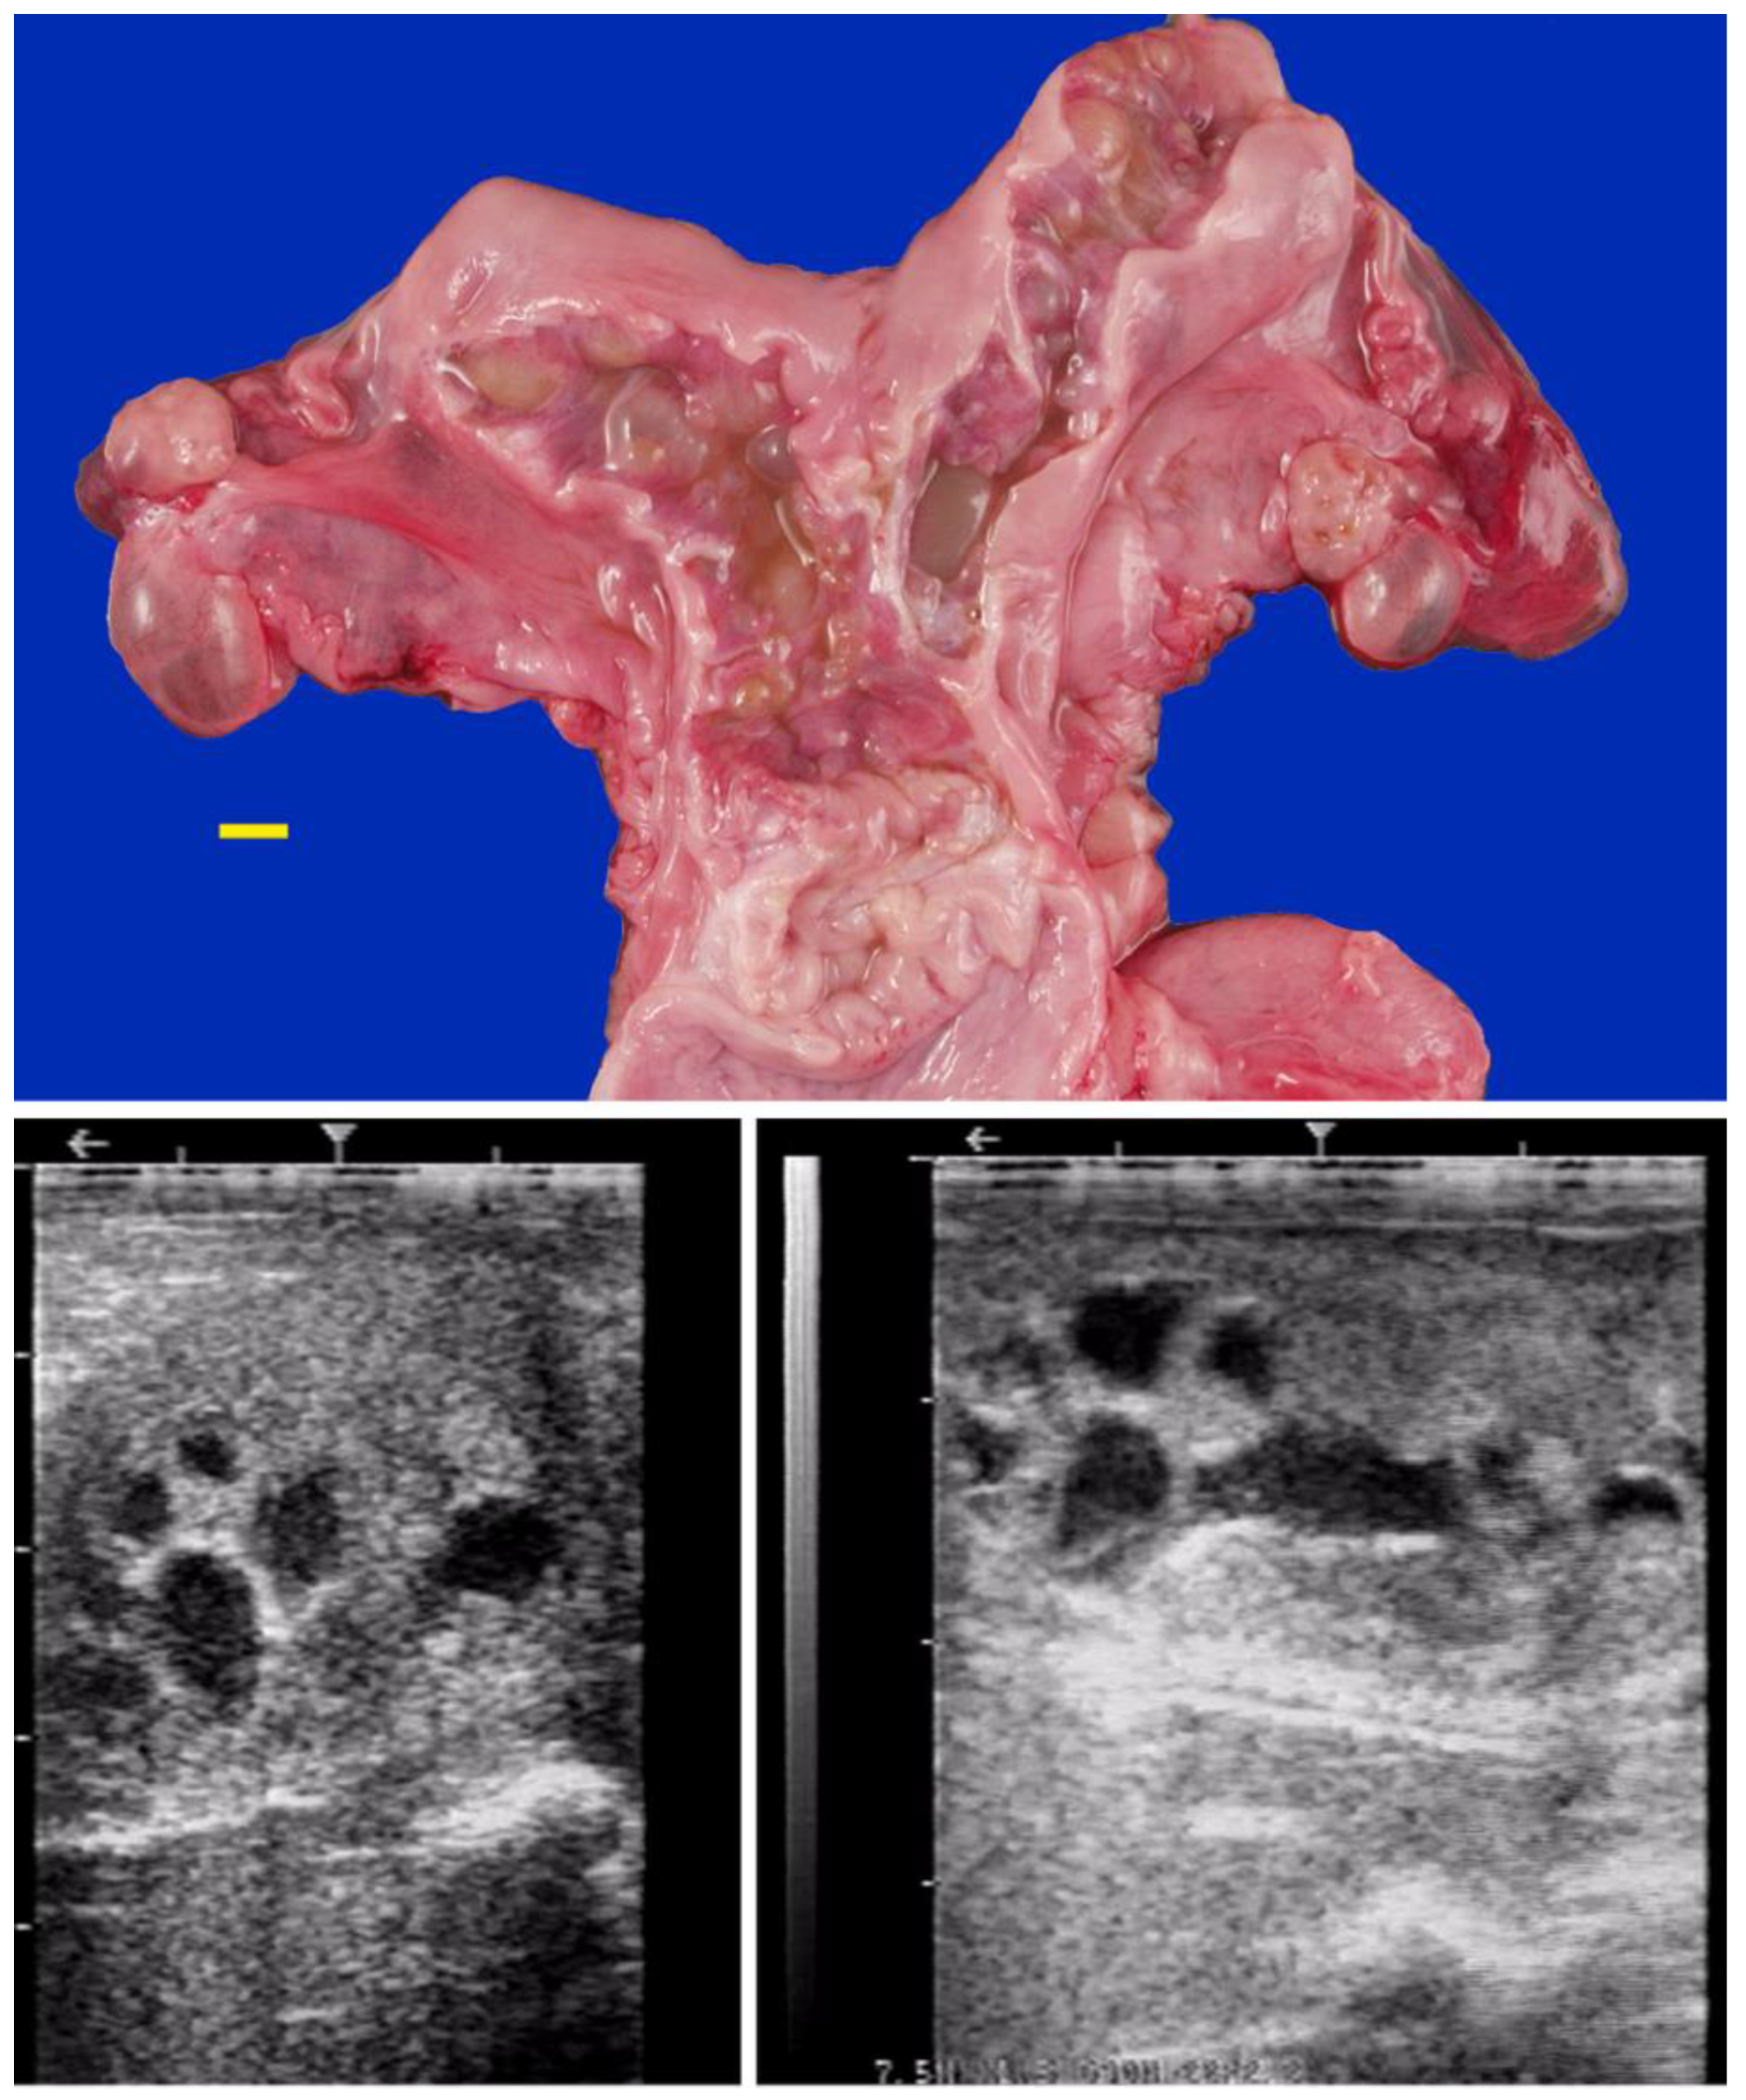

Hydrobursitis, or ovariobursitis, is a peculiar disorder in camels characterized by the accumulation of varying amounts of fluid within the ovarian bursa [44]. This pathology has been reported worldwide but appears to have a higher incidence in the Middle East [1,23,34,37,44,45]. The etiopathogenesis remains unclear. However, based on biochemical analysis of the fluid content, in some cases, the cause is attributed to recurrent ruptures of hemorrhagic follicles [44,46]. A variety of bacteria have been isolated (Actinobacillus spp., Escherichia coli, Klebsiella pneumoniae, Pseudomonas aeruginosa, Staphylococcus spp., and Streptococcus spp., as well as others) [46,47,48]. More recently, Chlamydophila abortus (Chlamydia abortus) infection has been demonstrated in several cases of hydrobursitis [49]. The role of Chlamydia spp., Brucella spp., and Campylobacter spp. in this pathology merits further investigation. Clinically, hydrobursitis is suspected when uterine retraction is not possible despite normal size of the uterus and cervix. Confirmation is easily obtained by transrectal or transcutaneous inguinal ultrasonography (Figure 6). Bilateral development is more frequent in females with long-standing infertility (more than 2 years) [44]. The main signs include repeat breeding, early embryo loss, and abortion [1,14,44,45]. Endometritis, uterine adhesions, and pyometra may also be diagnosed in cases of hydrobursitis [14,36,46]. Treatment with oxytetracycline (20 mg/kg IM for 7 days) combined with intrauterine infusion of metacresol sulfonic acid and formaldehyde solution was shown to be effective in restoring fertility if the lesion is small (<3 cm) [50]. Surgical excision of the affected side is the only treatment for large lesions (Figure 7) [44].

Figure 5. Gross appearance and ultrasonograms of anovulatory follicles in camels. (a) Thin-walled anovulatory follicle; (b) Thick-walled anovulatory follicle with some fibrin; (c) Hemorrhagic anovulatory follicle; (d) Luteinized anovulatory follicle.